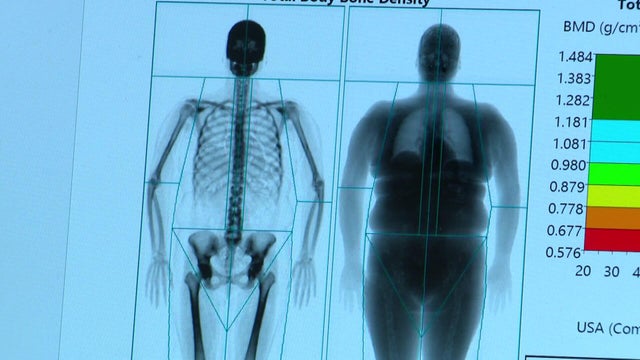

Jenn Glass has been taking a GLP-1 since last November. The 53-year-old mother of three has already lost more than 30 pounds, but she's focused on something beyond the number on the scale.